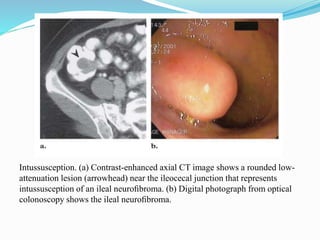

This document discusses colorectal polyps. It defines polyps and describes their types, including neoplastic and non-neoplastic polyps. It discusses adenomatous polyps in depth, noting their malignant potential increases with size over 1cm and villous architecture. Radiological diagnostic methods for polyps including single and double contrast barium enema and CT colonography are explained. The document provides an overview of polyp pathogenesis and genetic syndromes like FAP that increase cancer risk.